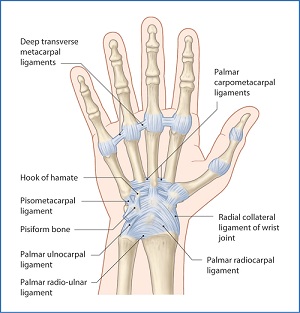

Hand & Wrist Preservation

The hand and wrist are a marvel of multiple small joints, facilitating intricate tasks like grasping objects, writing, or tying shoelaces. Given the daily wear and tear these essential tools endure, it's not unexpected that pain can arise, often due to overuse conditions like trigger finger or carpal tunnel syndrome. Additionally, sudden injuries are frequent in these delicate yet vital structures. Proper care and timely treatment are key to preserving their function.